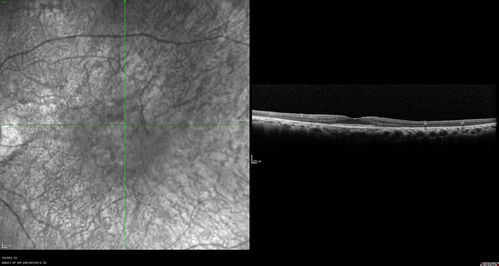

Radiation Retinopathy Both Eyes - 2023 - Two years after radiation for ocular lymphoma  (6)